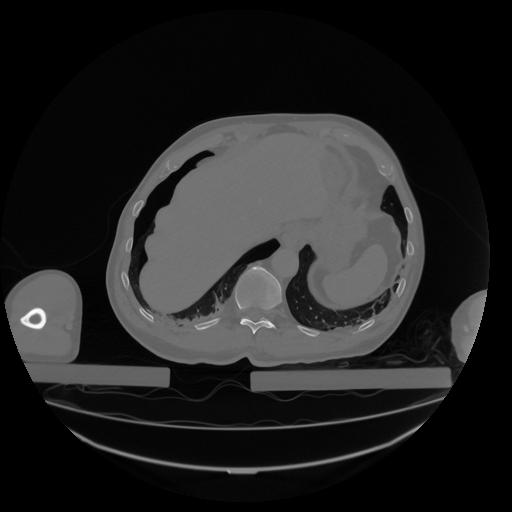

34 CUERPO,CE,Vol,1.0,CUERPO,,